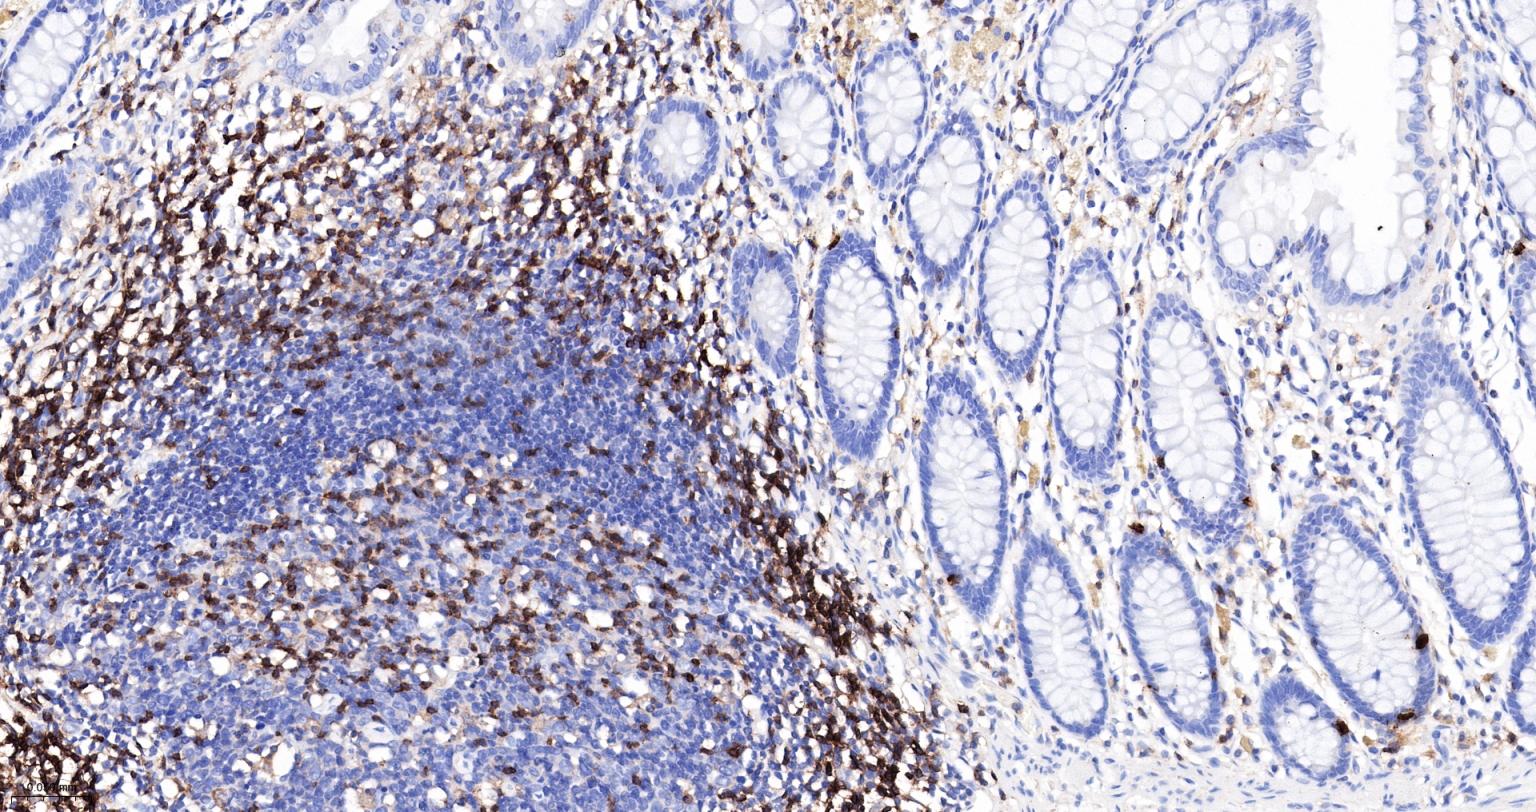

IHC-PHuman, Mouse, Rat1:500-2000

IHC-FHuman, Mouse, Rat1:500-2000